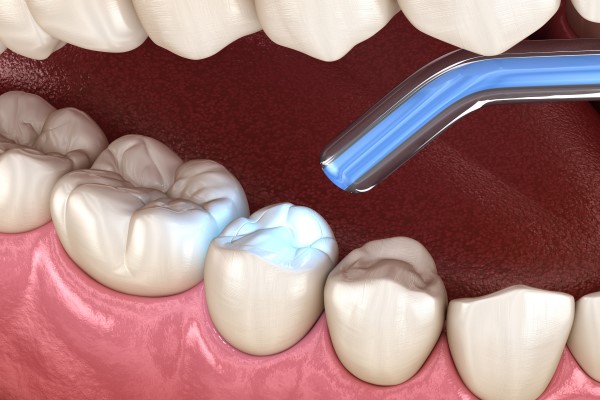

Fillings are used to treat a small hole, or cavity in a tooth.